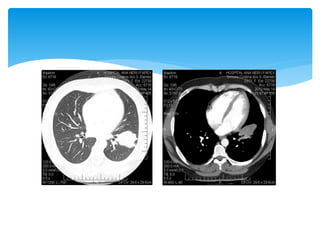

 TC de tórax: (11/07/12):

 lesão escavada, com limites parcialmente definidos

apresentando broncogramas de permeio no segmento

superior do lobo inferior esquerdo (dimensões: 5.3 x 3.4 cm).

 Massa na pirâmide basal anterior do lobo inferior esquerdo

apresentando atenuação heterogênea como imagens

hipoatenuantes em permeio que podem traduzir necrose/

cistificação.

 Pequeno nódulo com baixa atenuação no segmento superior

do lobo inferior direito medindo aproximadamente 1 cm de

diâmetro.